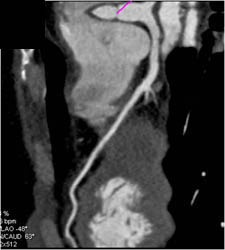

Normal Aortic Valve